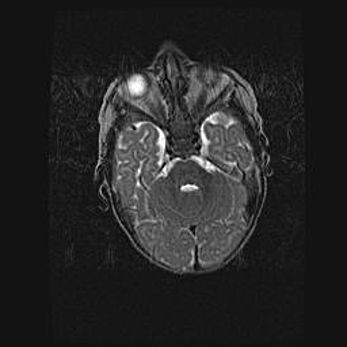

Подострая гематома правой гемисферы мозжечка.

Наружная гидроцефалия.

Возраст: 15 дней

Вес: 3100 г

Пол: женский

Окружность головы: 37 см

Срок гестации: 35-36 недель

При открытой наружной форме гидроцефалии у новорожденных расширяются и переполняются субарахноидные пространства.

Кровоизлияния в мозжечок имеют две клинико-анатомические формы: полушарные гематомы и кровоизлияния в червь.

К появлению этой патологии может привести: повреждения головного мозга, возникающие в результате асфиксии и гипоксии плода при беременности, или травмы во время родов. Редко гематома мозжечка может быть результатом первичной коагулопатии и сосудистой мальформации, диссеминированном внутрисосудистом свертывании, изоиммунной тромбоцитопении.